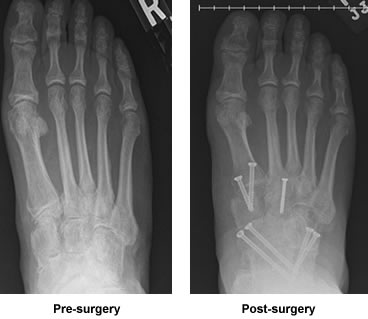

Let me back up and explain why I was so shocked and why I am now so grateful. I have struggled with osteoarthritis for years. At 49 I had bi-lateral knee replacements doing them both at once to just get it over with and get on with my life. That same year I had ankle surgery to remove bone spurs, it was not the first or last time surgeons had to go into my foot or ankle. After recovery from both those surgeries I had my active life back. During the last few years, things deteriorated to the point that despite numerous fluoroscopic guided injections they were unable to determine which mid-foot joint was causing me the most pain. Surgeons were looking for one, maybe two joints to fuse. Unable to pinpoint which were the worst we were at a stalemate and I limped away. I returned to my Podiatrist. He was alarmed at the condition of my foot and my gait. He gave me a boot to wear over the summer. I did find it gave more stability and I experienced less pain. Though it helped I developed a love hate relationship with it. It was hot and a real inconvenience. Because of the positive affect over the summer he prescribed an Arizona Brace with the hopes it would provide more practical pain relief and stability. He referred me to Dr. Leavitt to be fitted. That was my first appointment with Dr. Leavitt so imagine my surprise when he said "why would you wear a brace when I can fix you?"

I went home to think things over, returning with my husband to make sure I had actually heard him correctly and to discuss his plan and the recovery process. Dr. Leavitt was very thorough in his explanations, explaining the required two months non-weight bearing, one month partial weight bearing and months of physical therapy. Dr. Leavitt has explained that folks past the age of 60 often don't do well with major foot surgery that requires many months of disability and recovery. I decided that I wanted my life back and would go ahead with the procedure. I knew from past experience that is critical to follow all recommendations for recovery. It was strongly encouraged that I reacquaint myself with the use of crutches and recommended that I use a knee roller. His office staff kindly let me try out different brands of rollers from their storeroom. For me buying on-line was more cost efficient than renting. Before surgery we gathered "tools" that would help make me be as mobile as possible. I already had crutches, a walker and a raised potty. We borrowed a shower seat and wheel chair from the local Senior Center and installed a hand held showerhead.